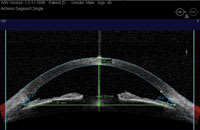

| Heidelberg slit lamp OCT of the anterior chamber angle. |

OCT of nasal and temporal sections of the anterior chamber angle including dimensions of key structures. |

The Stratus OCT (Carl Zeiss Meditec), used clinically for the evaluation of the retina, employs a 0.8 nm wavelength that cannot penetrate the sclera. As such, it is not ideal for assessing the anterior segment. However, the anterior segment version, the SL OCT, uses a longer wavelength that produces clinically useful results. Preliminary clinical studies suggest that anterior segment OCT compares favorably with conventional gonioscopy in its ability to identify potentially occludable angles.

The SL OCT allows for precise evaluation, measurement and analysis of the anterior segment, including anterior chamber depth (ACD), anterior chamber angles and the angle-to-angle distance (anterior chamber diameter). It can also assist in postoperative evaluation because it allows imaging and measurement of intraocular lenses and ocular implants.

The procedure is relatively fast. Additionally, you can perform it in complete darkness as well as in brightly lit surroundings (to assist in the dynamic assessment of the angle). The images are also digitally documented, so you can magnify, enhance, transmit and measure them. In addition, a technician can take the image, freeing the doctor to focus time on assessing the results. Compared with existing technology (ultrasound biomicroscopy), the anterior segment OCT does not contact the eye and provides a higher resolution image.